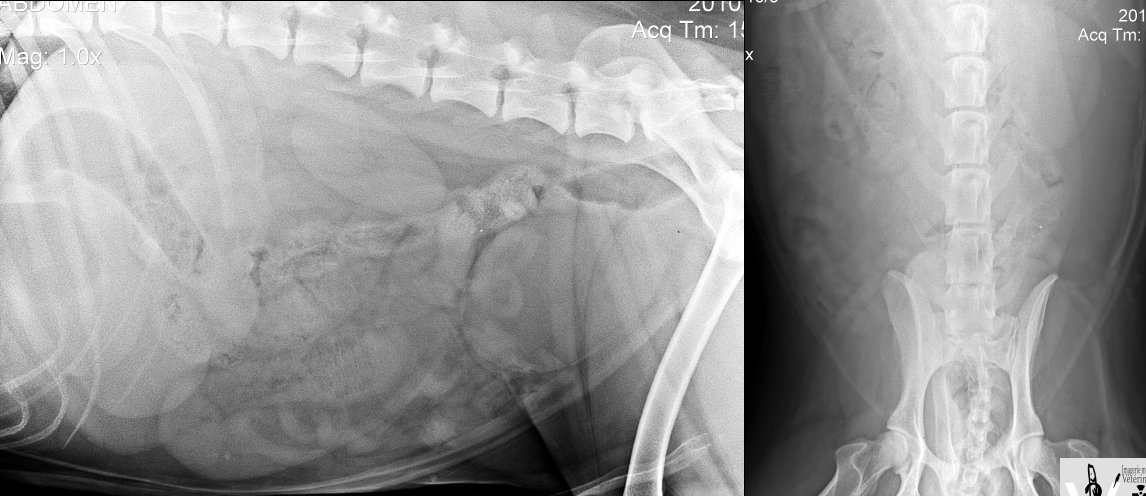

Cas 2: Charlot, un chien Labrador Retriever de 4 ans est présenté pour vomissements répétés depuis 2 jours

A. Obstruction mécanique secondaire à un CÉ

B. Gastroentérite

C. Pancréatite

D. Pyélonéphrite

A